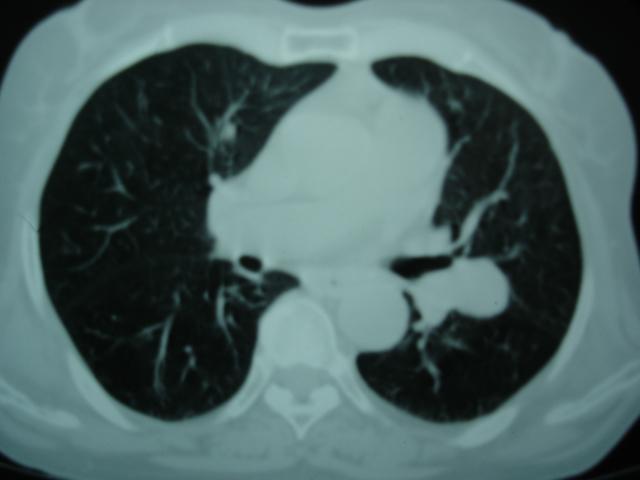

以下是引用卜一在2009-9-7 19:51:00的发言:[br][br] 1 左侧胸内甲状腺占位-多考虑甲状腺腺瘤! 2、左肺门占位-建议增强扫描以便明确性质。 3 慢支并感染! [br]

以下是引用shibing在2009-9-7 20:40:00的发言:[br]左侧胸内甲状腺占位-多考虑甲状腺腺瘤! 2、左肺门占位-建议增强扫描以便明确性质。 3 慢支并感染! [br]